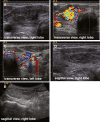

Case presentation: A 55 year-old, caucasian man presented with overt hyperthyroidism (thyrotropin (TSH) <0.01 μIU/L; free thyroxine (FT4) 3.03 ng/dL), negative thyroid peroxidase and thyroglobulin autoantibodies, but elevated thyroid stimulating hormone receptor antibodies (TSH-RAb 2.6 IU/L). Ultrasound showed a highly vascularized hypoechoic nodule (1.1 × 0.9 × 2 cm) in the right lobe, which projected onto a hot area detected in the 99mtechnetium thyroid nuclear scan. Overall uptake was increased (4.29%), while the left lobe showed lower tracer uptake with no visible background-activity, supporting the notion that both Graves' disease and a toxic adenoma were present. After normal thyroid function was reinstalled with methimazole, the patient underwent thyroidectomy. Histological work up revealed a unifocal papillary microcarcinoma (9 mm, pT1a, R0), positively tested for the BRAF V600E mutation, embedded into the hyperfunctional nodular goiter.